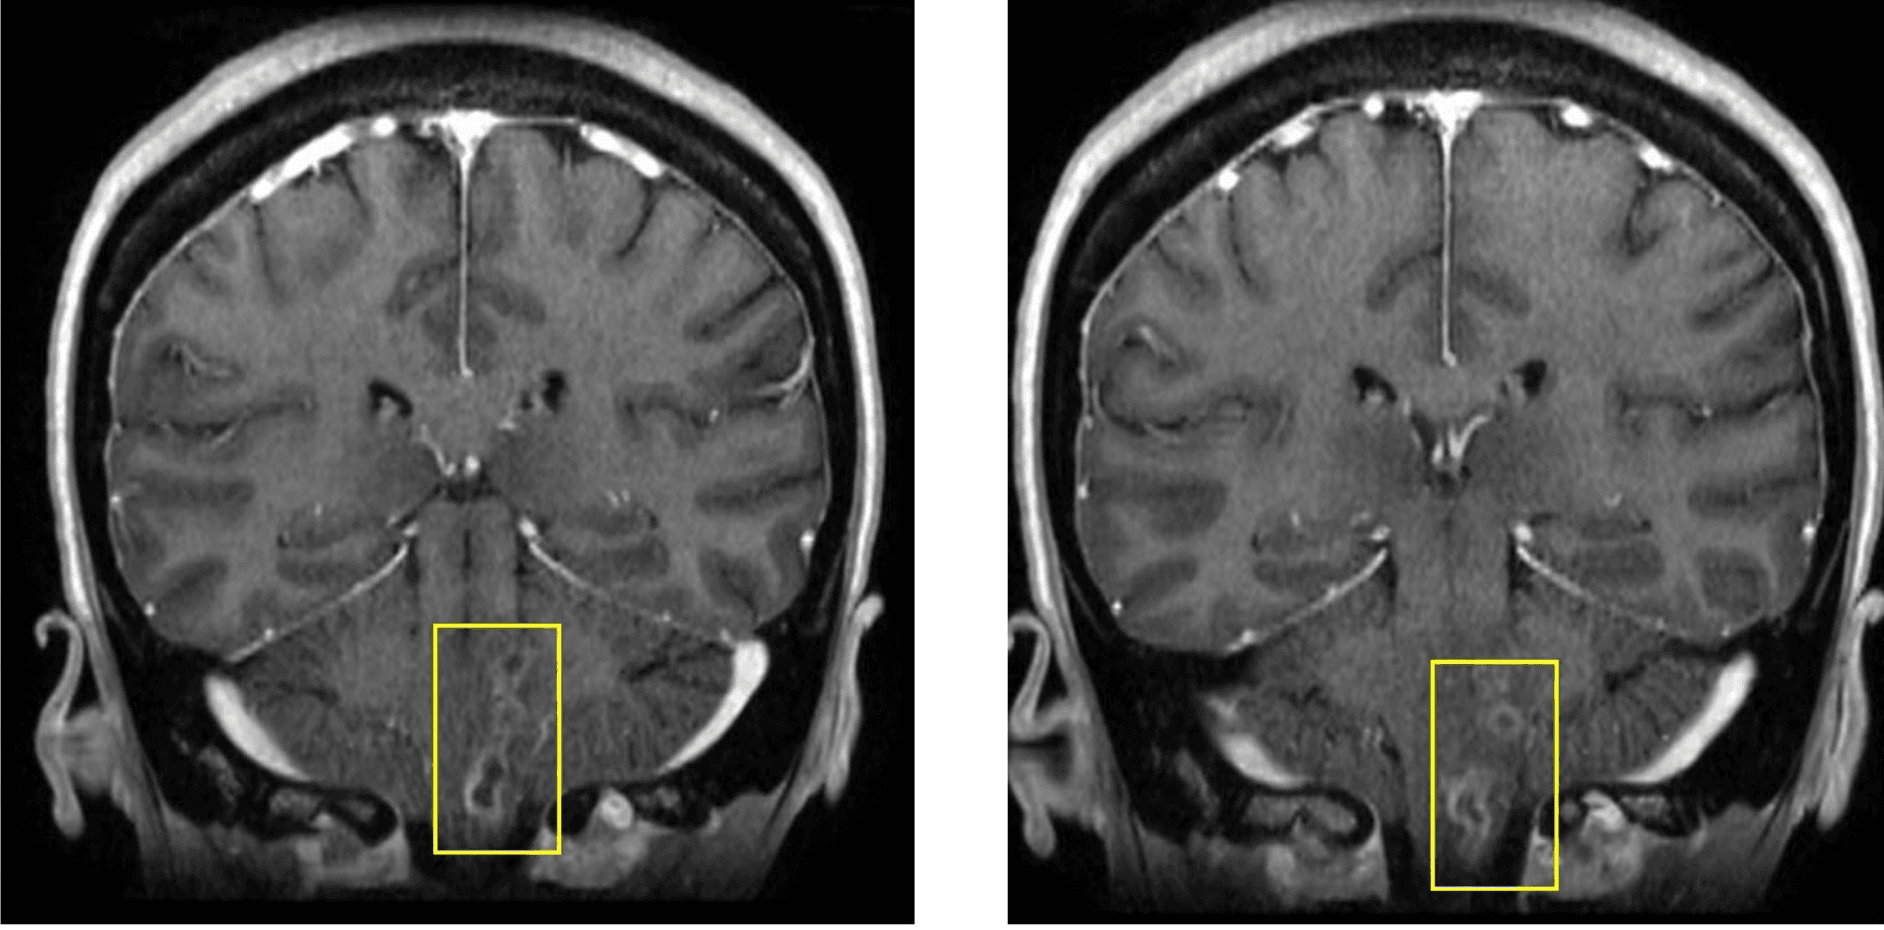

Lumbar puncture shows CSF white cells 144 cells/microL (neutrophil-predominant), protein 134 mg/dL, and glucose 48 mg/dL. Gram stain and early cultures are negative. MRI brain with contrast demonstrates multifocal enhancing lesions in a tract-like pattern involving the medulla and dorsal pons, with enhancement near lower cranial nerve root entry zones.

Contrast-enhanced brain MRI